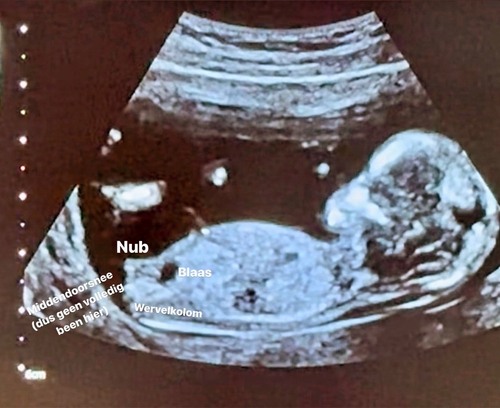

Hier is de nub dus niet goed te zien. Meer het been = dus niet door het midden.

(Blaas wel mooi in beeld ;-))